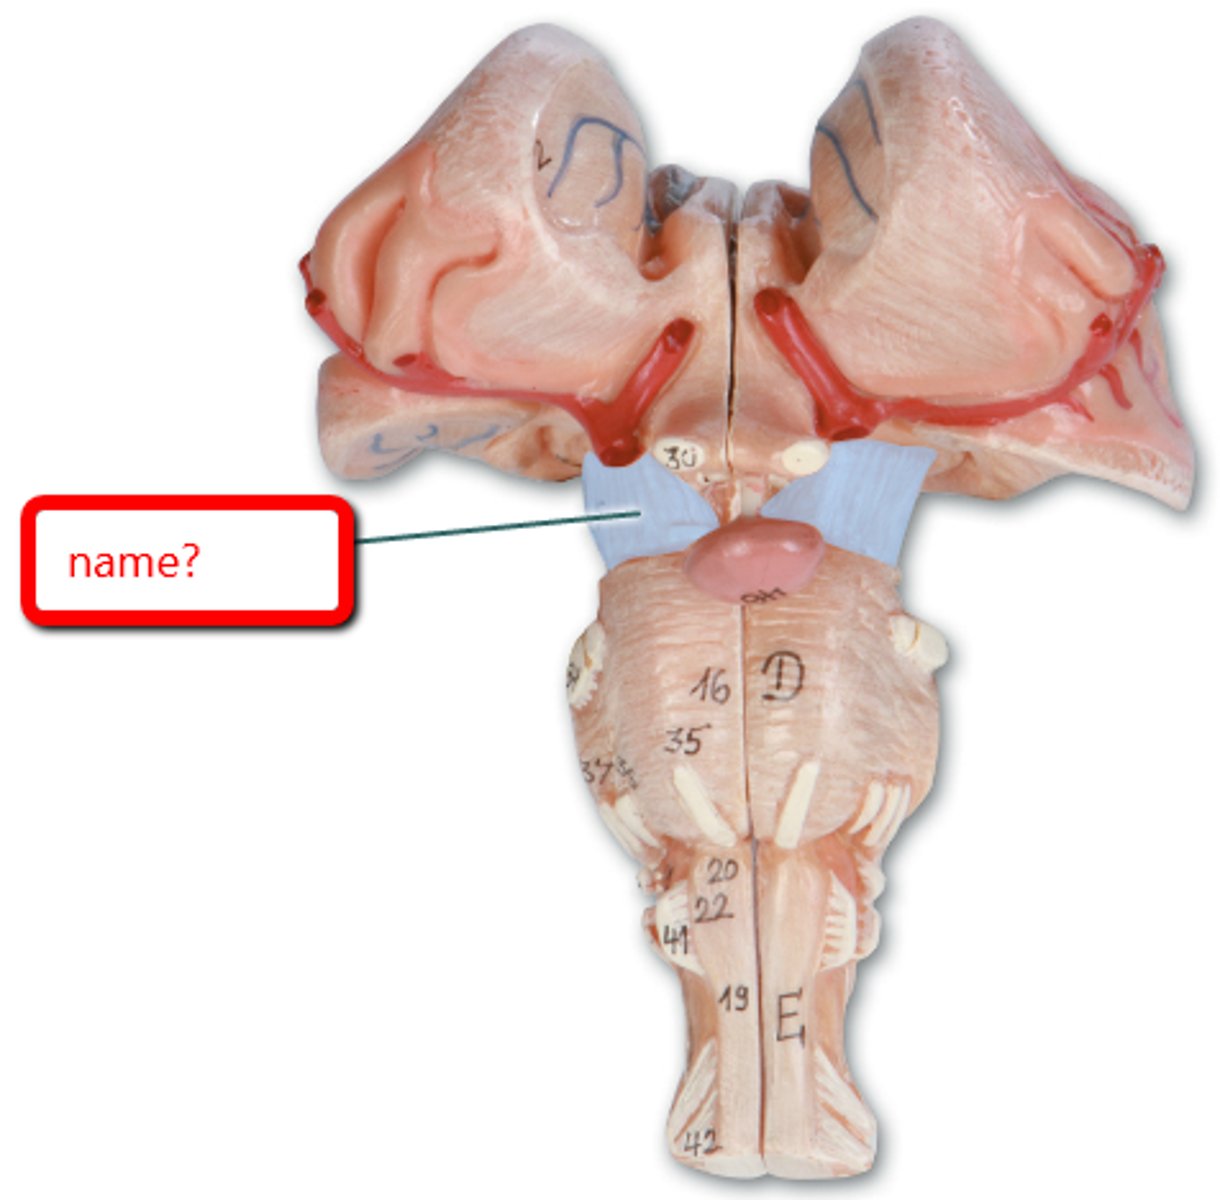

optic chiasm

optic nerve

optic tract